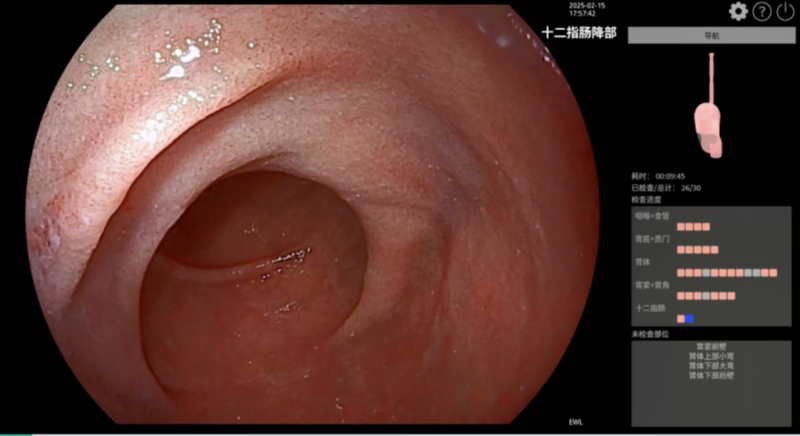

▲常规冻结(上)与智能预冻结(下)AI辅助质控与诊断:目前在上、下消化道检查时,iEndo均可使用开立自研内镜AI功能,辅助内镜医生进行临床诊断。比如,用于上消化道检查的AI胃部质控功能,使用时屏幕会实时显示模拟的胃部三维渲染图像,显示当前检查部位、已检部位以及未检部位,并以不同颜色标记,以便医者实时了解检查进度。

▲AI胃部质控功能在下消化道肠部辅助质控功能中,AI内镜可以智能识别回盲瓣,并提醒操作医生保持退镜速度的稳定性,降低视野盲区。而清洁度监测功能,将自动监测肠道清洁度,实时计算当前部位的清洁度评分。